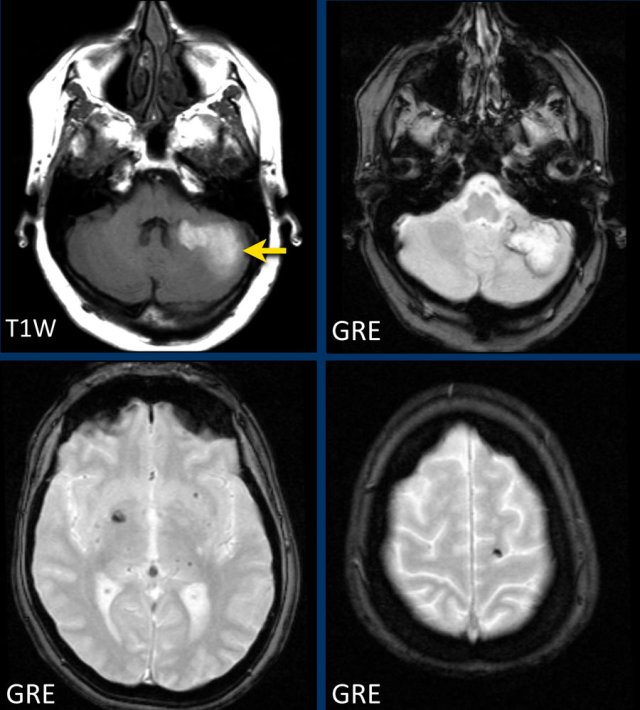

This patient presented with a cerebellar hemorrhage.

The gradient echo-images show multiple microbleeds.

This can be the result of long standing hypertension due to the central location of some of the microbleeds.

This patient presented with a cerebellar hematoma.

Continue with the T1W-image...

The T1W-image shows a hyperintense hemorrhage (arrow).